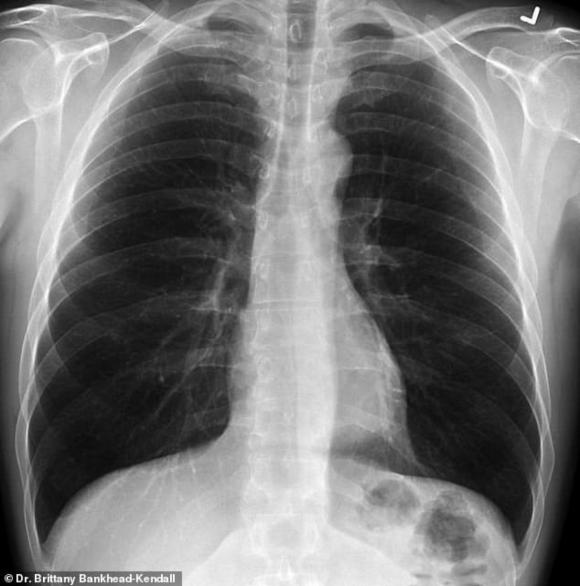

Phim của người khỏe mạnh có nhiều khoảng đen, cho thấy họ có thể hít vào đủ lượng oxy cần thiết. Phim chụp phổi người hút thuốc thì có nhiều khoảng mờ, còn của bệnh nhân Covid-19 thì gần như trắng xóa.

Phổi khỏe mạnh. Ảnh: Bác sĩ Kendall.